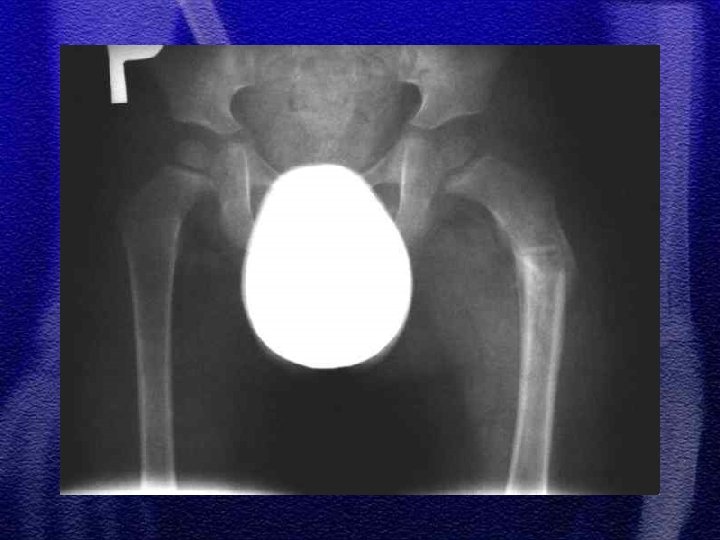

§ Dotyczy najczęściej chłopców w wieku 4 -10 lat § Złamanie występuje najczęściej w środkowej części trzonu § Dziecko jest we wstrząsie z powodu bólu i dużej utraty krwi , musi być hospitalizowane § Należy pamiętać o możliwości współistnienia zwichnięcia stawu biodrowego, złamania panewki lub miednicy § Złuszczenie nasady bliższej kości udowej urazowe występuje głównie u noworodków i niemowląt

§ Do 4 roku życia leczenie wyłącznie zachowawczewyciąg plastrowy lub szkieletowy w zależności od wieku § Większość złamań do 10 r. ż. - wyciąg szkieletowy ok. 3 tyg. , a następnie gips biodrowy od 3 do 6 tygodni w zależności od wieku § Leczenie operacyjne rozważa się po 10 roku życia a metody zespolenia to: Zespol, pręty Endera, Rusha, stabilizatory zewnętrzne

§ Częstym zjawiskiem występującym po złamaniach trzonu kości udowej u dzieci jest przerost (w zakresie uda) kończyny na długość § Przyczyną przerostu kończyny jest przekrwienie kości w wyniku złamania i nadmiernego pobudzenia chrząstek wzrostowych § Różnica długości kończyn może dochodzić do 2 cm

§ Noworodki i niemowlęta - tolerancja załamania osi 30 -40°, 1, 2 cm skrócenia § U dzieci starszych tolerancja załamania osi< 20°, przemieszczenia do boku przebudowują się § Lecząc wyciągiem szkieletowym (trwa to ok. 3 tyg. ) należy wystrzegać się nadmiernego rozciągnięcia odłamów (przerost na długość)